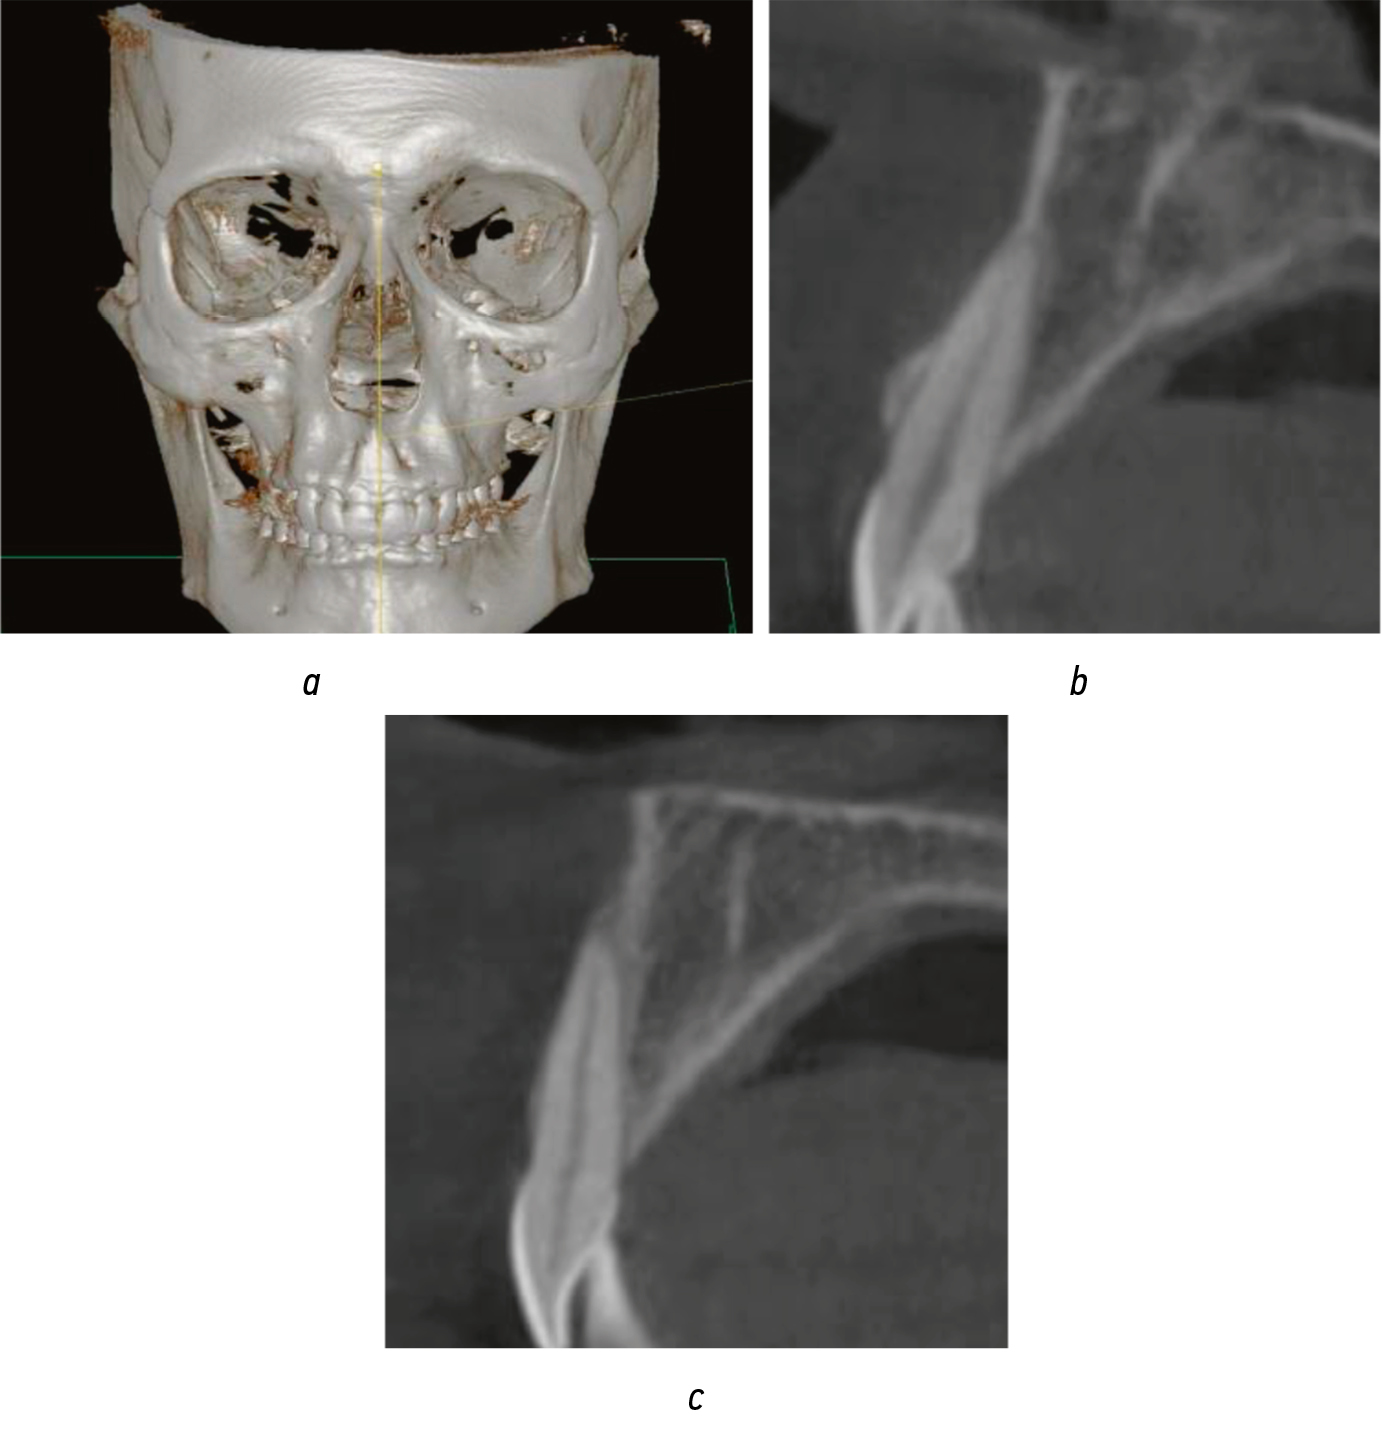

CBCT assessed for dehiscence and fenestrations, including their distribution in different teeth, as these limited torque selection (Fig. 1a). Sagittal slices were evaluated for localized dehiscence or fenestration affecting specific teeth (Fig. 1b, c). Data were entered into each patient’s medical record.

Fig. 1. Cone-beam tomography of a patient with distoclusion: (a) 3D reconstruction (16×16 cm); (b) sagittal section with fenestration of tooth 1.2; (c) sagittal section with dehiscence of tooth 2.1

Рис. 1. Конусно-лучевая томография пациента с дистооклюзией: а — 3D-реконструкция 16×16 см; b — сагиттальный срез с фенестрацией зуба 1.2; с — сагиттальный срез с дегисценцией зуба 2.1